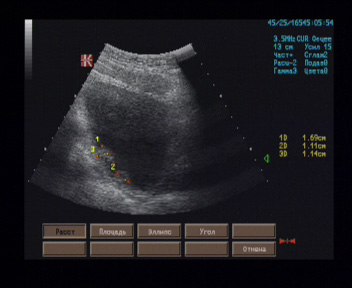

Мочевой пузырь симметричной овальной формы, наружные контуры ровные, V мочи 300 мл, стенка толщиной 5 мм, на внутренней поверхности задней стенки лоцируются два изогипоэхогенных образования, расположенные вблизи шейки, в 12 мм друг от друга, размерами 15 х 11 х 19 мм и 12 х 10 х 9 мм, а также двух узлов в проекции шейки – размерами 12 х 9 х 9 мм и передней стенки вблизи шейки размерами 19 х 15 х 13 мм, имеющие широкие основания, овальные формы, однородное внутреннее строение, на остальном протяжении внутренняя поверхность пузыря гладкая, просвет свободный.

Эхографические признаки многофокусного новообразования мочевого пузыря.